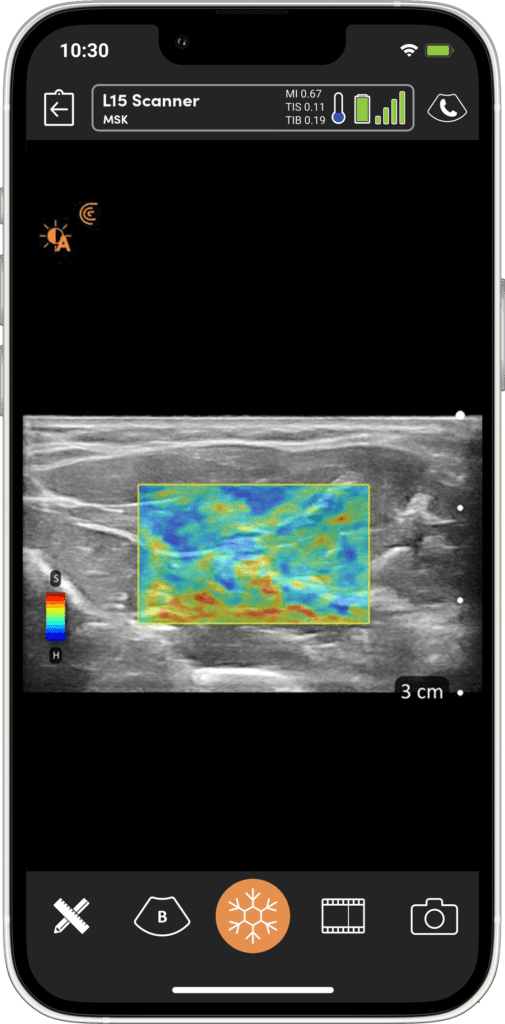

Mesurez et visualisez les informations clés du flux à travers une interface simple et intuitive.